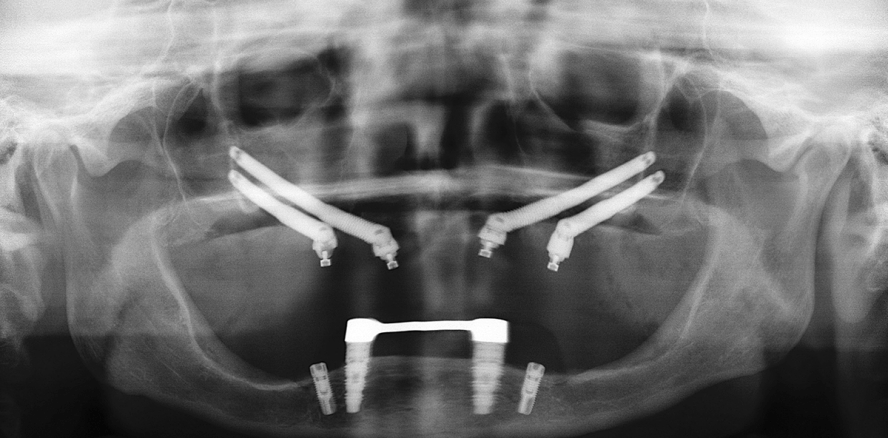

Im Zuge der Implantatinsertion wurde zunächst das anteriore Implantat (Brånemark Zygoma TiUnite 4,0 x 50 mm, 40 Ncm) auf Höhe des lateralen Inzisivus präpariert, um die Orbita bzw. den Nervus infraorbitalis zu schonen, dann das posteriore (Brånemark Zygoma TiUnite 4,0 x 40 mm, 50 Ncm) Implantat an der Position des zweiten Prämolaren bzw. ersten Molaren.

Eine umgekehrte Vorgehensweise würde eine erhebliche größere Verletzungsgefahr der orbitalen Strukturen mit sich bringen. Dies verdeutlicht umso mehr, dass die Kenntnis der anatomischen Strukturen der Zygoma- und Orbitaregion eine Conditio sine qua non für das Quad-Zygoma-Protokoll ist. Analog dazu wurde auf der linken Seite verfahren: Zunächst wurde ein Schleimhaut­periostlappen präpariert, sodass Sinus­wand, Nervus infraorbitalis und Zygoma dargestellt wurden. Auch hier gelang es, die Kieferhöhlenschleimhaut ohne Perforation zu elevieren und nach medial einzuschlagen. Anterior wurden ein Zygoma-Implantat TiUnite 4,0 x 47,5 mm, posterior ein ­Zygoma-Implantat der Göße 4,0 x 35 mm inseriert. Beide Implantate konnten mit einem Drehmoment von 50 Ncm eingebracht werden.

Vor Nahtverschluss erfolgte die Auswahl der Multi-Unit-Abutments unter Knochensicht und Beurteilung des Weich­gewebsangebots. Für Regio 12 wurde ein gerades Multi-Unit-Abutment von 3 mm Höhe, Regio 15 ein 17 Grad anguliertes Abutment von 3 mm Höhe, Regio 22 ein gerades MultiUnit-Abutment von 3 mm Höhe, Regio 25 ebenfalls ein anguliertes Abutment von 5 mm Höhe gewählt. Anschließend wurden die Wundränder mit resorbierbarem Nahtmaterial (5/0 Glycogen, ­RESORBA) reponiert und verschlossen. Auf beiden Seiten wurde aufgrund der intakten Sinus- und Schleimhautstrukturen auf GBR- und/oder GTR-Maß­nahmen verzichtet.